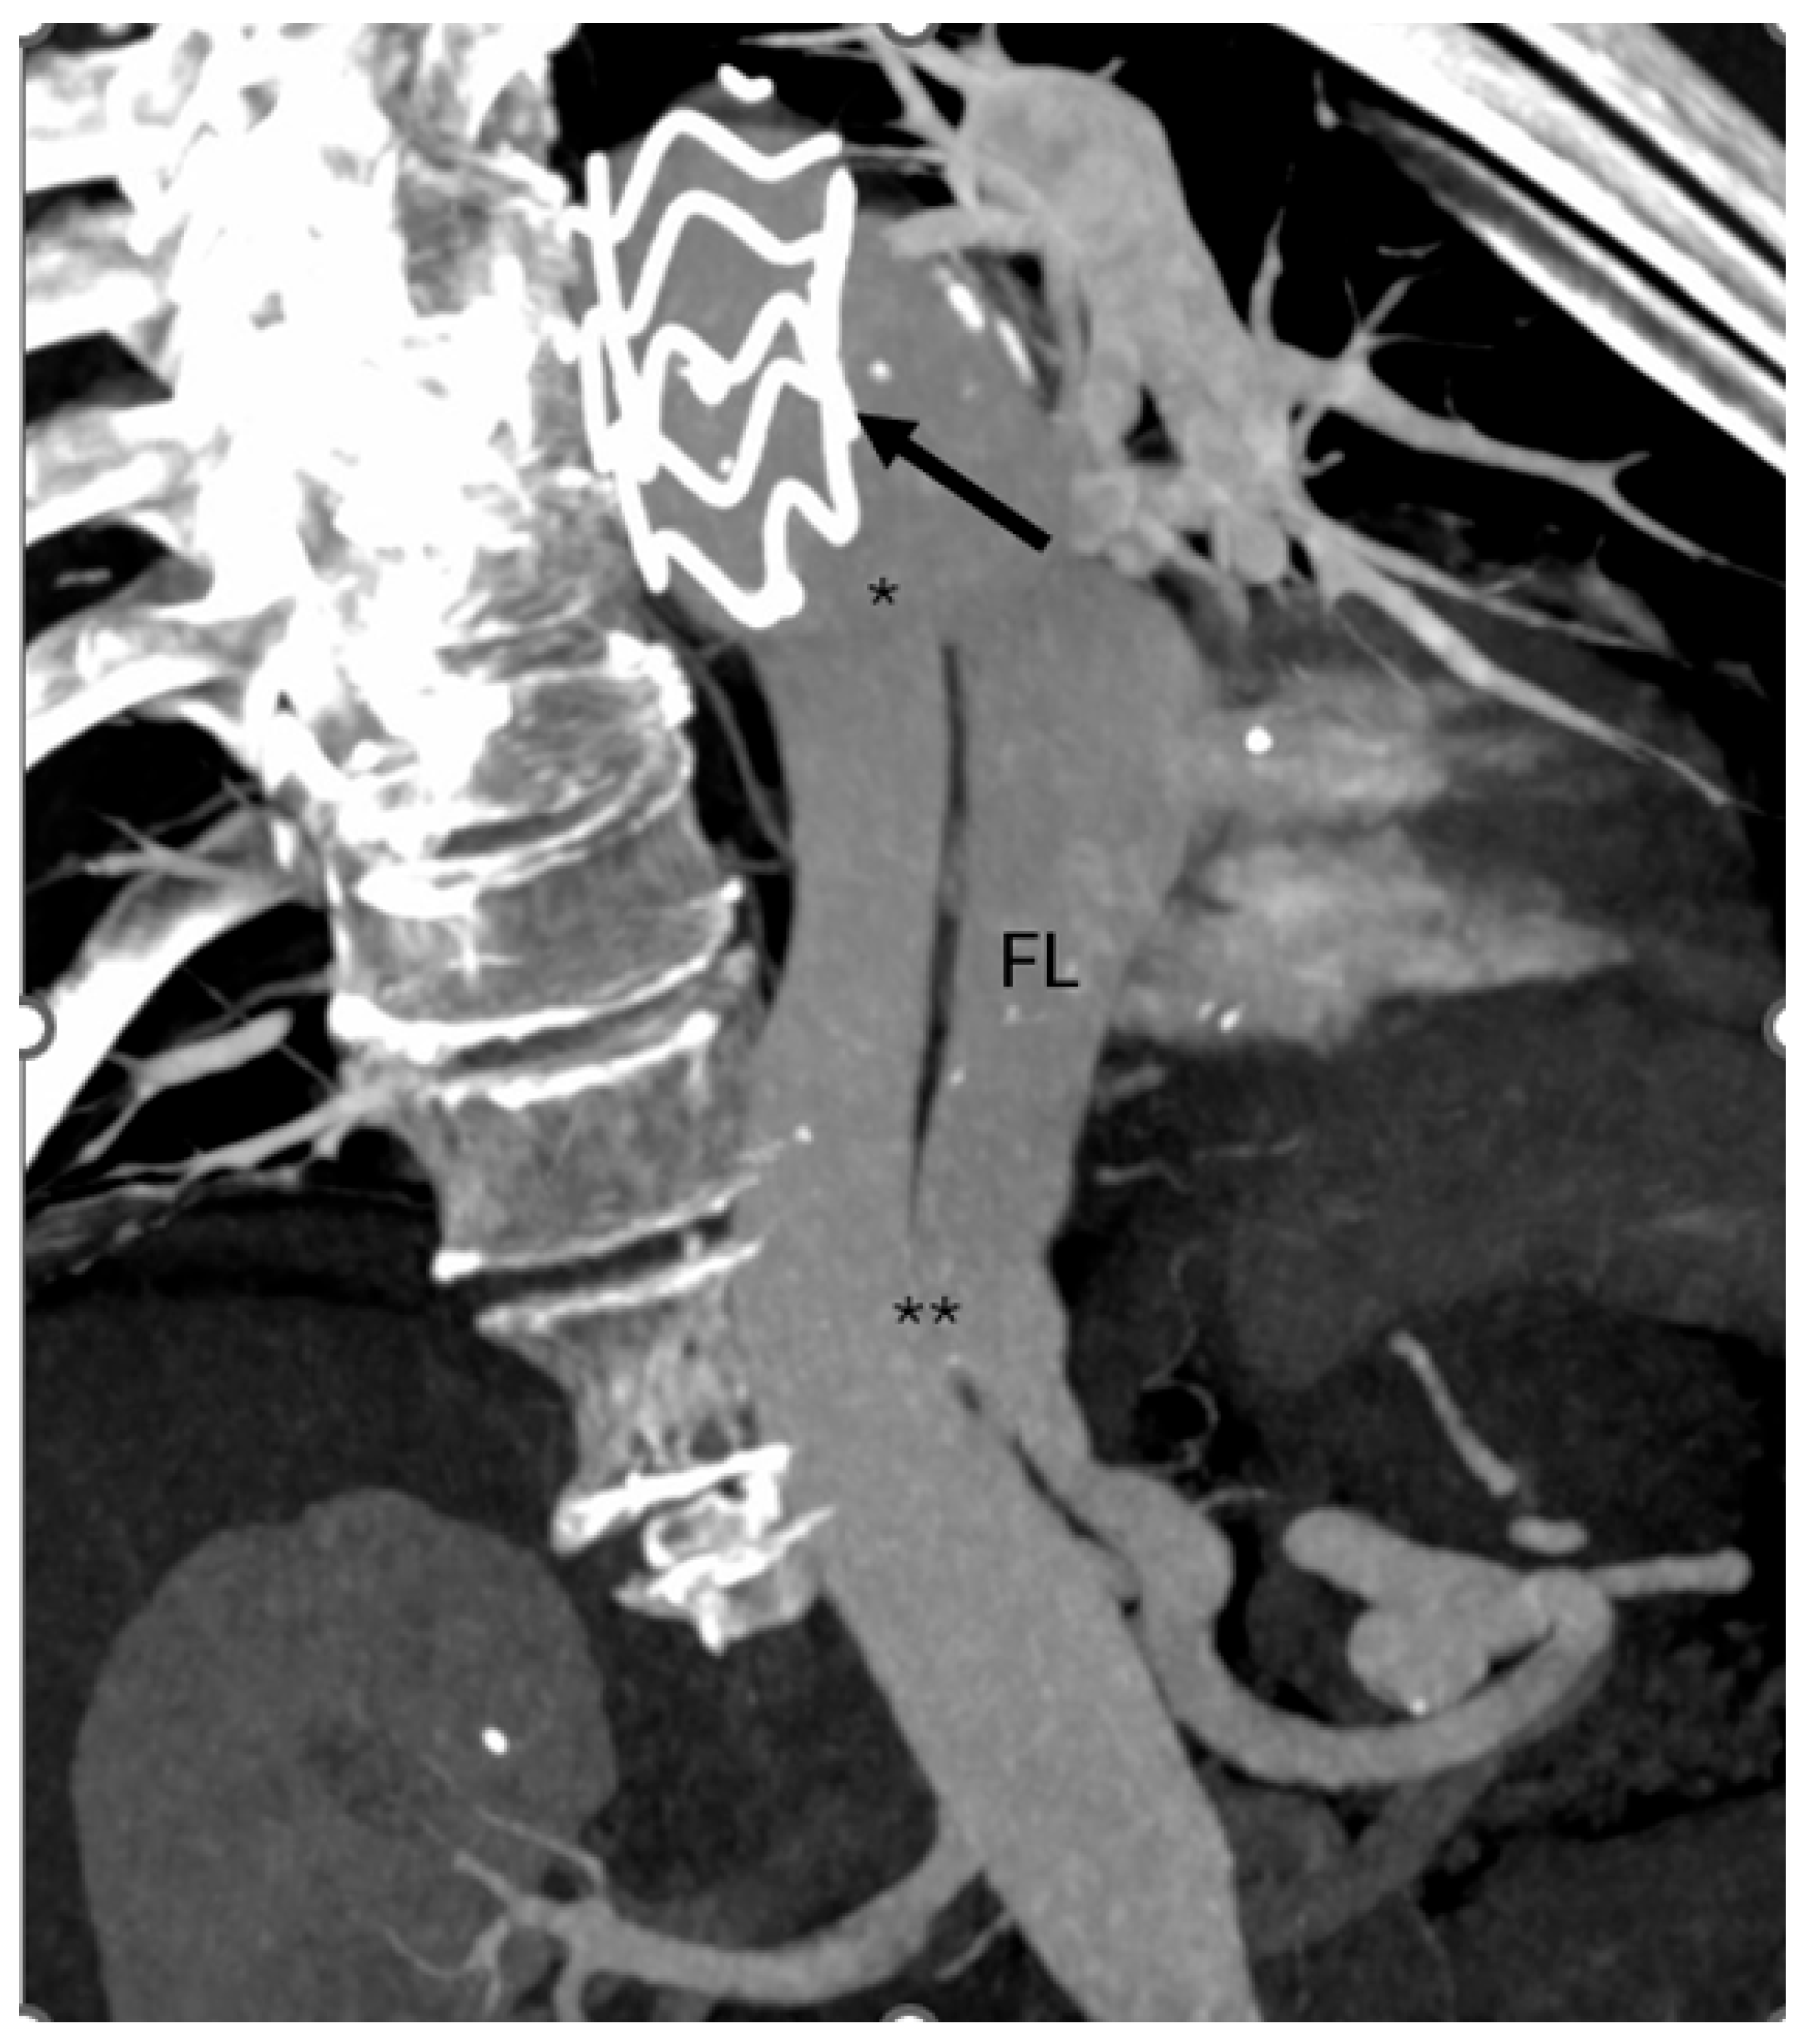

Follow-up computed tomography angiography (CTA) carried out in June 2025 revealed recanalization of the FL, extending from the distal aortic arch (zone 3) to the level of the superior mesenteric artery (zones 6–7). The descending thoracic aorta (DTA) demonstrated aneurysmal degeneration, with a maximum diameter of 58.5 mm (Figure 1).

Figure 1. Computed tomography angiography (CTA) showing prior TEVAR (arrow) with recanalization of the false lumen (FL) through a proximal tear (*) near the stent graft and a distal tear (**) in zones 6–7.